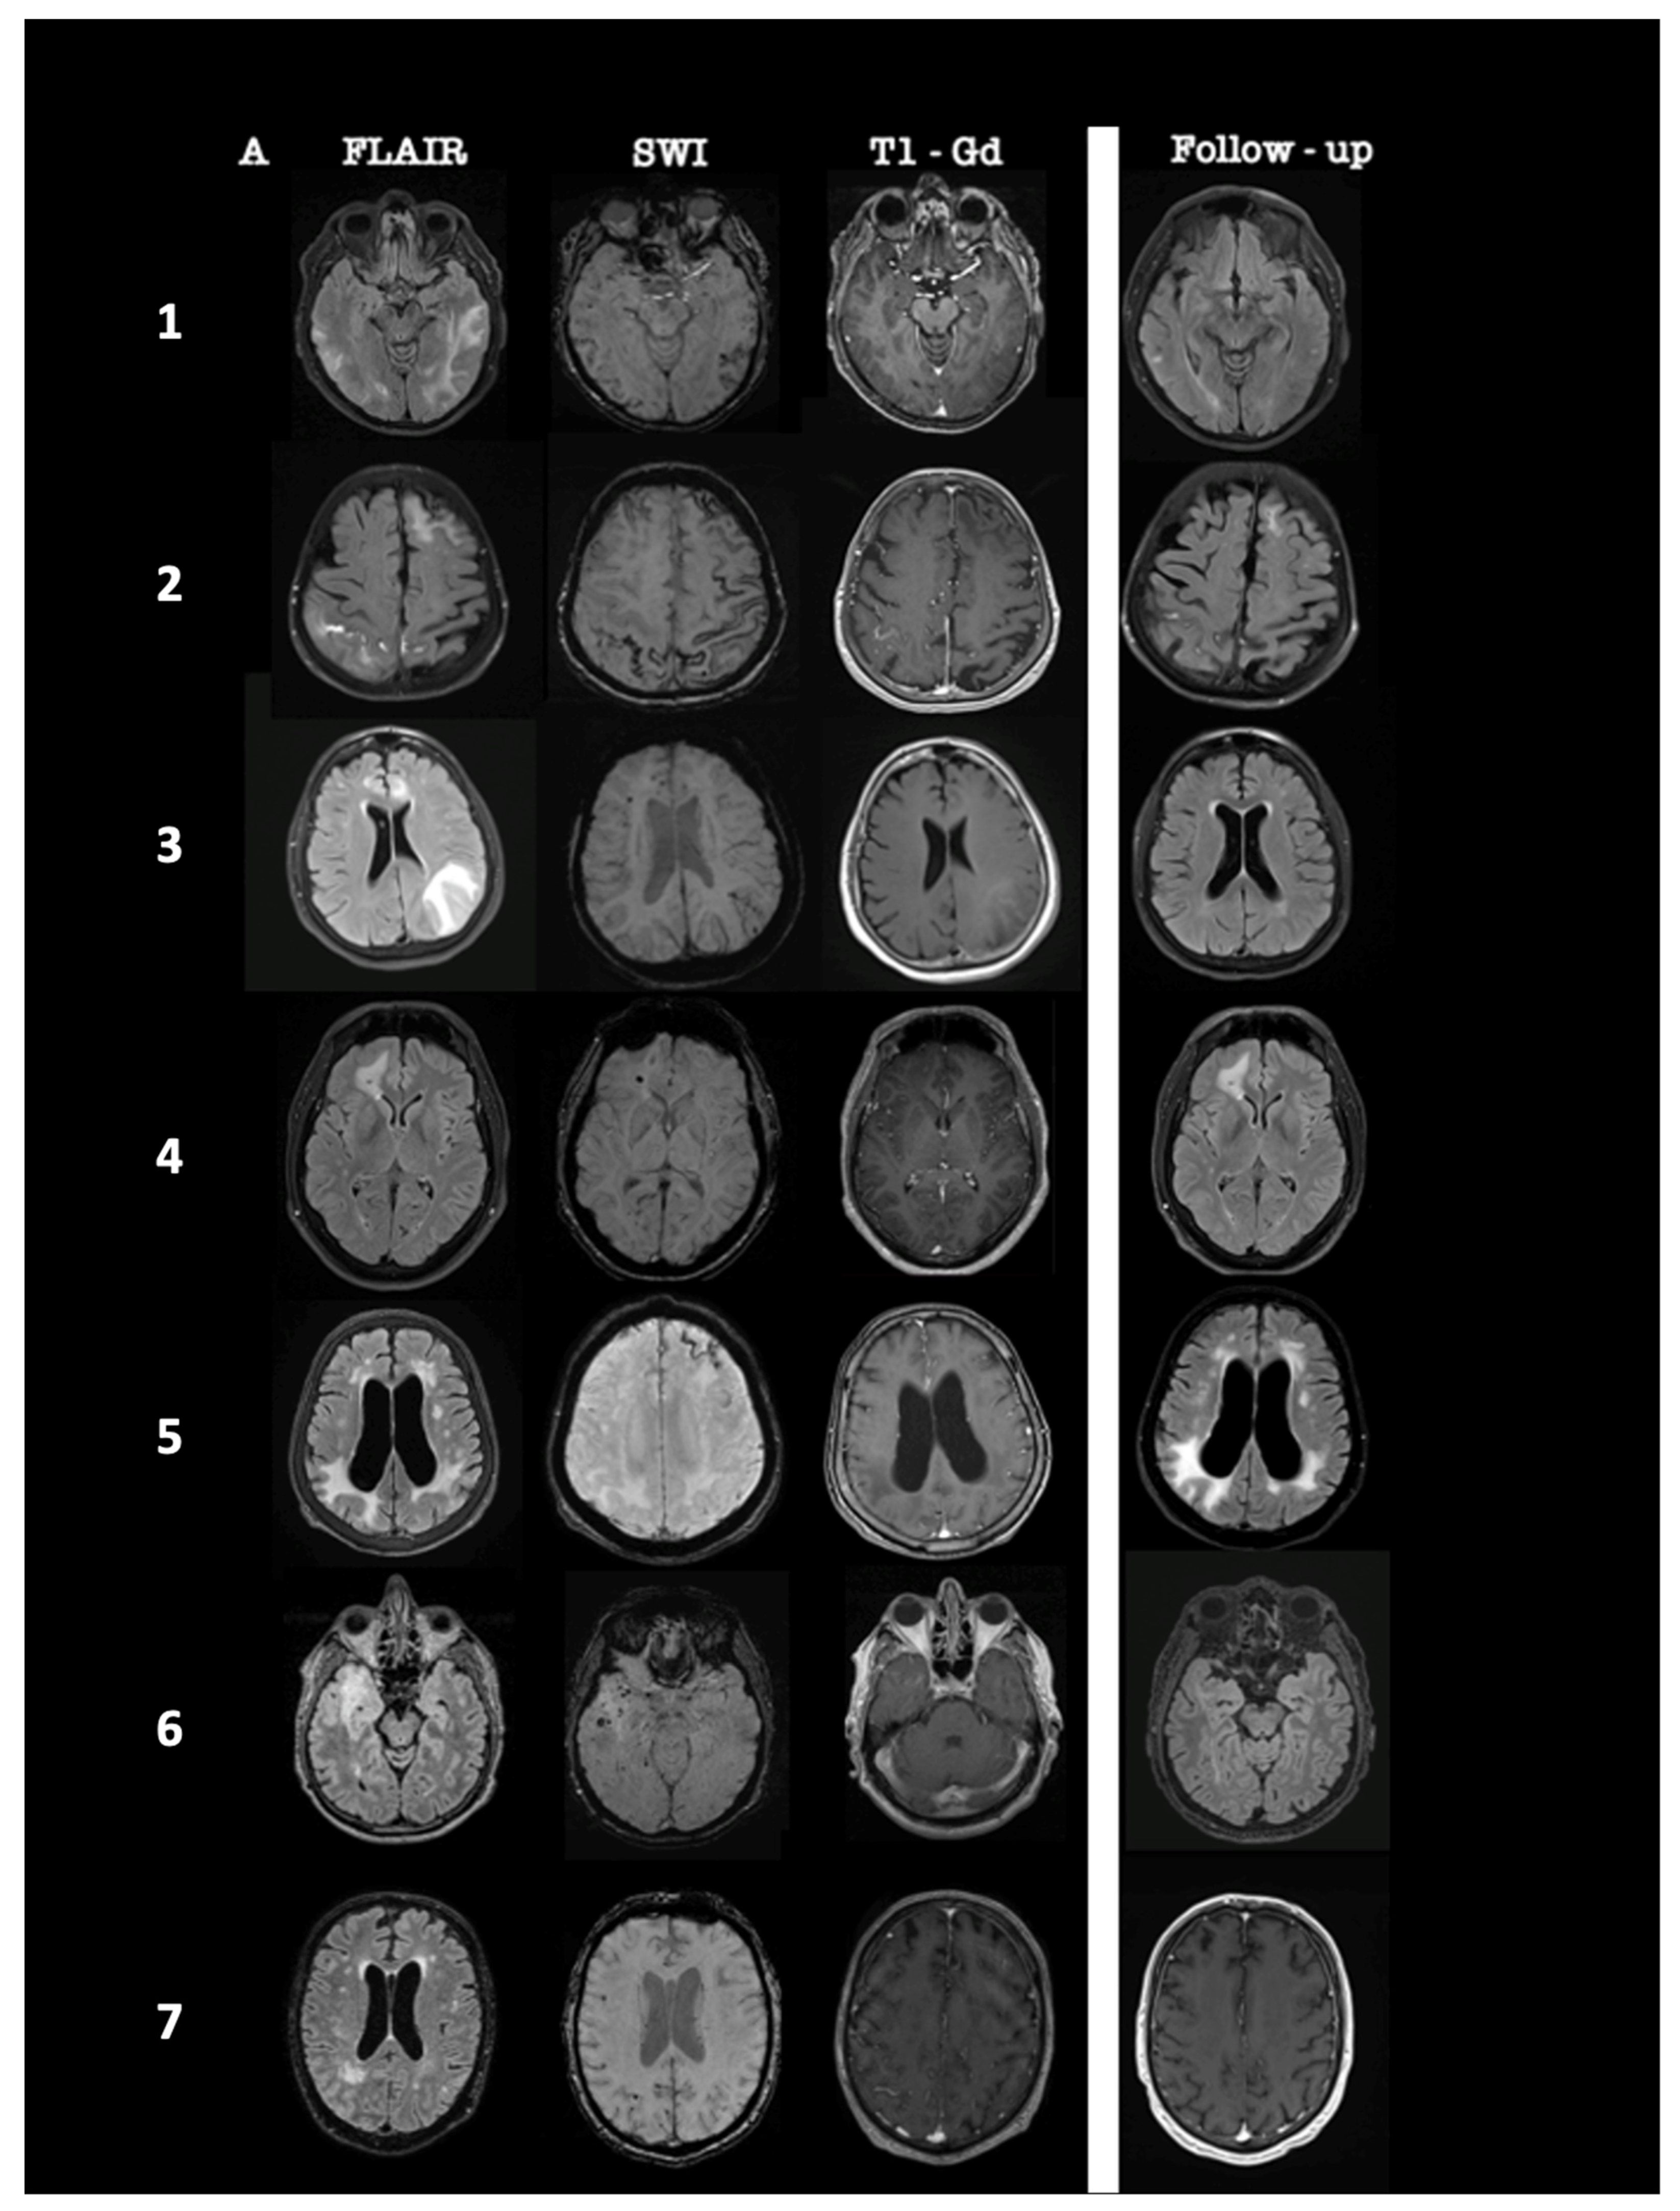

The most prevalent radiological findings were the following: T2/FLAIR white matter hyperintensities (100%, unifocal 43%, multifocal 57%), cerebral microbleeds (71%), and gadolinium-enhancing T1-lesions (71%). SWI sequences revealed disseminated cortical superficial siderosis (CSS) in one patient, whereas another patient presented with subacute convexity subarachnoid hemorrhage (CSAH) in the right parietal lobe. A summary of the MRI findings of all patients at diagnosis and 1-month follow-up post-treatment initiation is presented in Figure 1.

Figure 1.

Summary of brain MRI characteristics of 7 patients at diagnosis and one month after treatment initiation. MRI findings of patients #1 to #7 are ordered from the top to the bottom. At diagnosis, axial fluid-attenuated inversion recovery (FLAIR) sequences showed supratentorial white matter lesions, multifocal in patients #1, #2, #3, and #5 and unifocal in patients #4, #6, and #7. In patients #1, #3, #4, #6, and #7, these lesions were associated with multiple cortical and subcortical cerebral microbleeds on Susceptibility Weighted Images, whereas patient #2 demonstrated left frontal cortical superficial siderosis (CSS) and subacute cortical subarachnoid hemorrhage (CSAH) on the right parietal lobe, and disseminated CSS was depicted on patient #5. White matter lesions on patients #2, #3, #4, #6, and #7 were associated with parenchymal or leptomeningeal contrast enhancement. In patients #1, #2, #3, #4, #5, and #6, follow-up axial FLAIR sequence one month after corticosteroid initiation showed a marked regression of hyperintense lesions on patients #1, #2, #3, and #6 and a stable size of hyperintense lesions on patients #4 and #5. In patient #7, the follow-up axial post-gadolinium T1 sequence revealed a complete resolution of gadolinium enhancement.

Brain MRI was performed one month after treatment initiation, and in four patients #1, #2, #3, #6, the neuroimaging examination revealed a nearly complete resolution of the T2/FLAIR hyperintense white matter lesions. Two patients #4, #5 showed only partial or mild resolution of the white matter lesions, which remained stable in the next follow-up MRIs at 3, 6, and 12 months. In one patient #7, contrast-enhanced T1-weighted MRI sequences revealed complete resolution of gadolinium enhancement 3 months after corticosteroid initiation. Five patients #1, #2, #3, #4, #5 were clinically and radiologically stable after 12 and 24 months of follow-up, and one patient #2 died due to severe COVID-19 pulmonary infection 18 months after diagnosis.